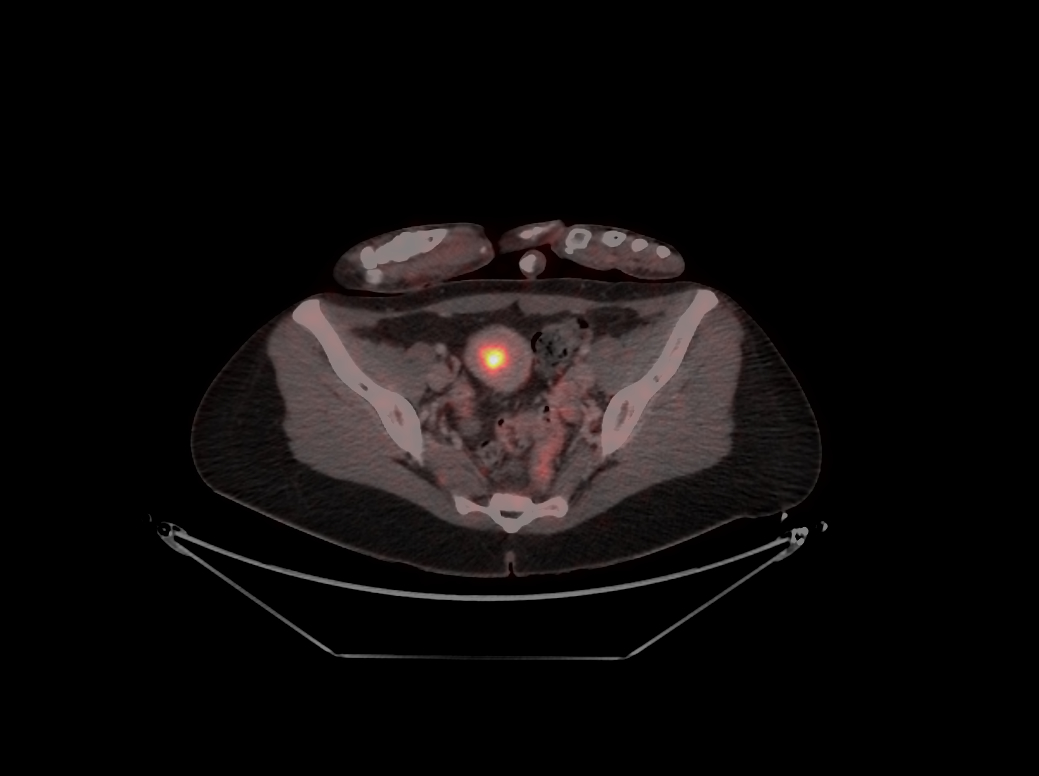

Innsbruck, am 27.11.2024: Das Endometriumkarzinom (Gebärmutterkörperkrebs) ist die häufigste Krebserkrankung der weiblichen Genitalorgane und im frühen Stadium gut behandelbar. Die Herausforderung liegt im fortgeschrittenen Stadium (III und IV) und bei wiederkehrender Erkrankung, eine platinhaltige Chemotherapie ist hier das Mittel der Wahl. Gynäkologische Forschungsbestrebungen gehen dahin, die wirksame, aber belastende Chemotherapie durch neue Immun- und Kombinationstherapien zu unterstützen oder zu ersetzen.